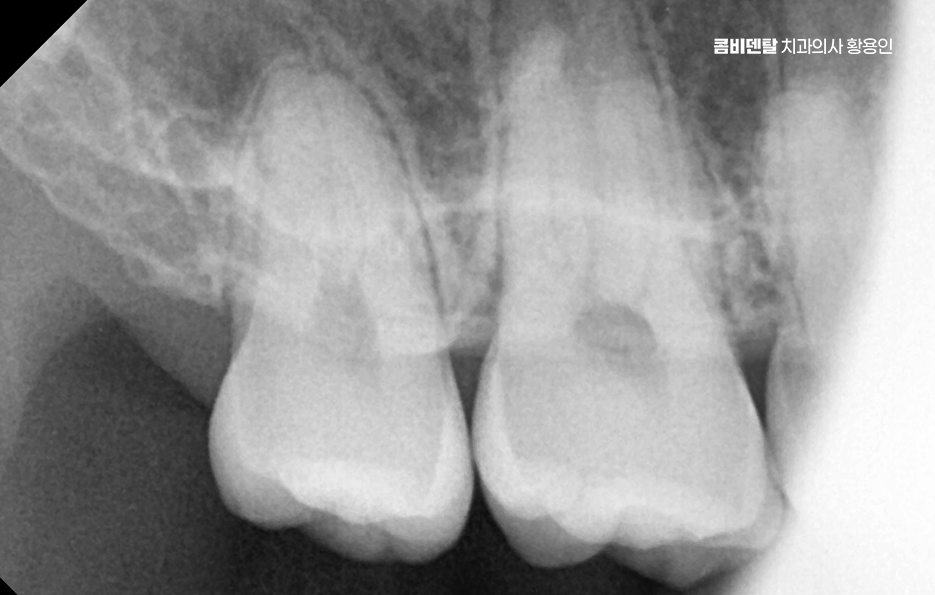

매복된 사랑니는 겉으로 보이지 않기 때문에 대부분의 경우 증상이 없다고 생각하기 쉬운데 매복된 사랑니 주변은 세균이 쉽게 모이고 염증이 생기기 쉬운 구조로서 완전히 뼈 속에 묻혀 있어도 턱 안쪽에서 염증 반응이 시작되면 얼굴 붓기, 통증, 구취, 심할 경우 턱관절이나 림프절까지 부어오르는 일이 생길 수 있어요.

여기에 더해서 신경과의 거리도 문제로 아래턱에는 하치조신경이라는 굵은 감각신경이 지나가는데 완전 매복사랑니의 뿌리가 이 신경과 가까이 위치해 있는 경우가 많아서 만약 발치 중 이 신경을 건드리거나 손상이 생기면, 입술이나 턱 끝 부위에 감각 이상이 생길 수 있어요.

완전매복사랑니 발치 그래서 무조건 바로 뽑는다고 되는 게 아니라, 사전에 정밀한 진단과 영상검사가 꼭 필요하며 일반적인 파노라마 사진 외에도 CT 촬영을 통해 신경과의 거리, 뿌리의 형태, 턱뼈의 두께 등을 정밀하게 확인해야 발치 계획을 안전하게 세울 수 있었어요.

요즘은 디지털 기반의 정밀 검진을 통해서 치료 전부터 철저한 준비가 가능하며 발치를 아무리 정교하더라도 개개인의 회복력이나 건강 상태에 따라 차이가 생길 수 있기 때문에, 사전 진단과 수술 후 관리까지 철저하게 준비해야 안전한 발치가 가능하다는 점에 대해서 잘 알고 계획하는 것이 중요하며 정리해서 완전 매복사랑니는 겉으로는 보이지 않지만 내부에서 다양한 문제를 유발할 수 있고, 특히 신경과 가깝거나 뼈에 깊이 박혀 있는 경우 발치가 어렵고 위험할 수도 있어서 문제를 일으키기 전에 미리 진단을 받고, 정기적인 검진을 통해서 보다 현명하게 치료 계획을 세워보시길 바라고 있어요